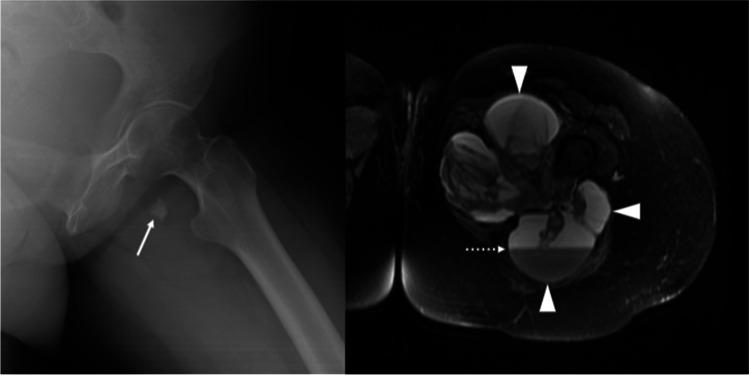

New molecular insights are being achieved in synovial sarcoma (SS) that can provide new potential diagnostic and prognostic markers as well as therapeutic targets. In particular, the advancement of research on epigenomics and gene regulation is promising. The concrete hypothesis that the pathogenesis of SS might mainly depend on the disruption of the balance of the complex interaction between epigenomic regulatory complexes and the consequences on gene expression opens interesting new perspectives. The standard of care for primary SS is wide surgical resection combined with radiation in selected cases. The role of chemotherapy is still under refinement and can be considered in patients at high risk of metastasis or in those with advanced disease. Cytotoxic chemotherapy (anthracyclines, ifosfamide, trabectedin, and pazopanib) is the treatment of choice, despite several possible side effects. Many possible drug-able targets have been identified. However, the impact of these strategies in improving SS outcome is still limited, thus making current and future research strongly needed to improve the survival of patients with SS.